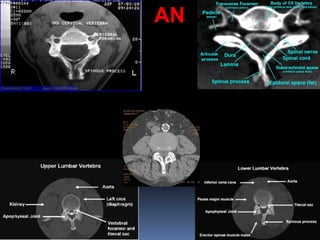

Cross-Sectional Anatomy

of the Spinal Cord

Computerized Tomographic

Imaging

CT

PHYSICAL PRINCIPLES OF COMPUTED TOMOGRAPHY

PHYSICAL PRINCIPLES OFCOMPUTED TOMOGRAPHY AN